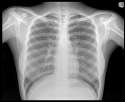

[8 / 6 / ?] 184KiB, 1080x720, tumblr_npm1w3IPA21qkcf9xo1_1280.jpg View SameGoogleImgOpsiqdbSauceNAO Anonymous Wed 28 Oct 2015 15:10:34 No.13889982 ViewReplyReportDelete Quoted By: Can anyone x-ray? Subject Name E-mail Password